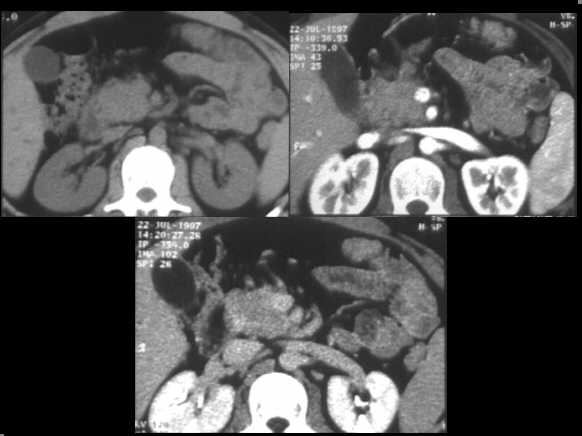

Cystic dystrophy of the duodenal wall – solid variant. Spiral CT examination in the venous contrastographic phase shows a thick, solid sheet-like mass between the duodenum and the pancreatic head. The fibrotic tissue is clearly hypodense in comparison to the pancreatic parenchyma.

Focal autoimmune pancreatitis of the head. Spiral CT examination, before and after c.m. administration, demonstrates an enlarged head, which appears hypodense in the arterial contrastographic phase towards the spleen. Hypodensity remains appreciable in the venous phase.